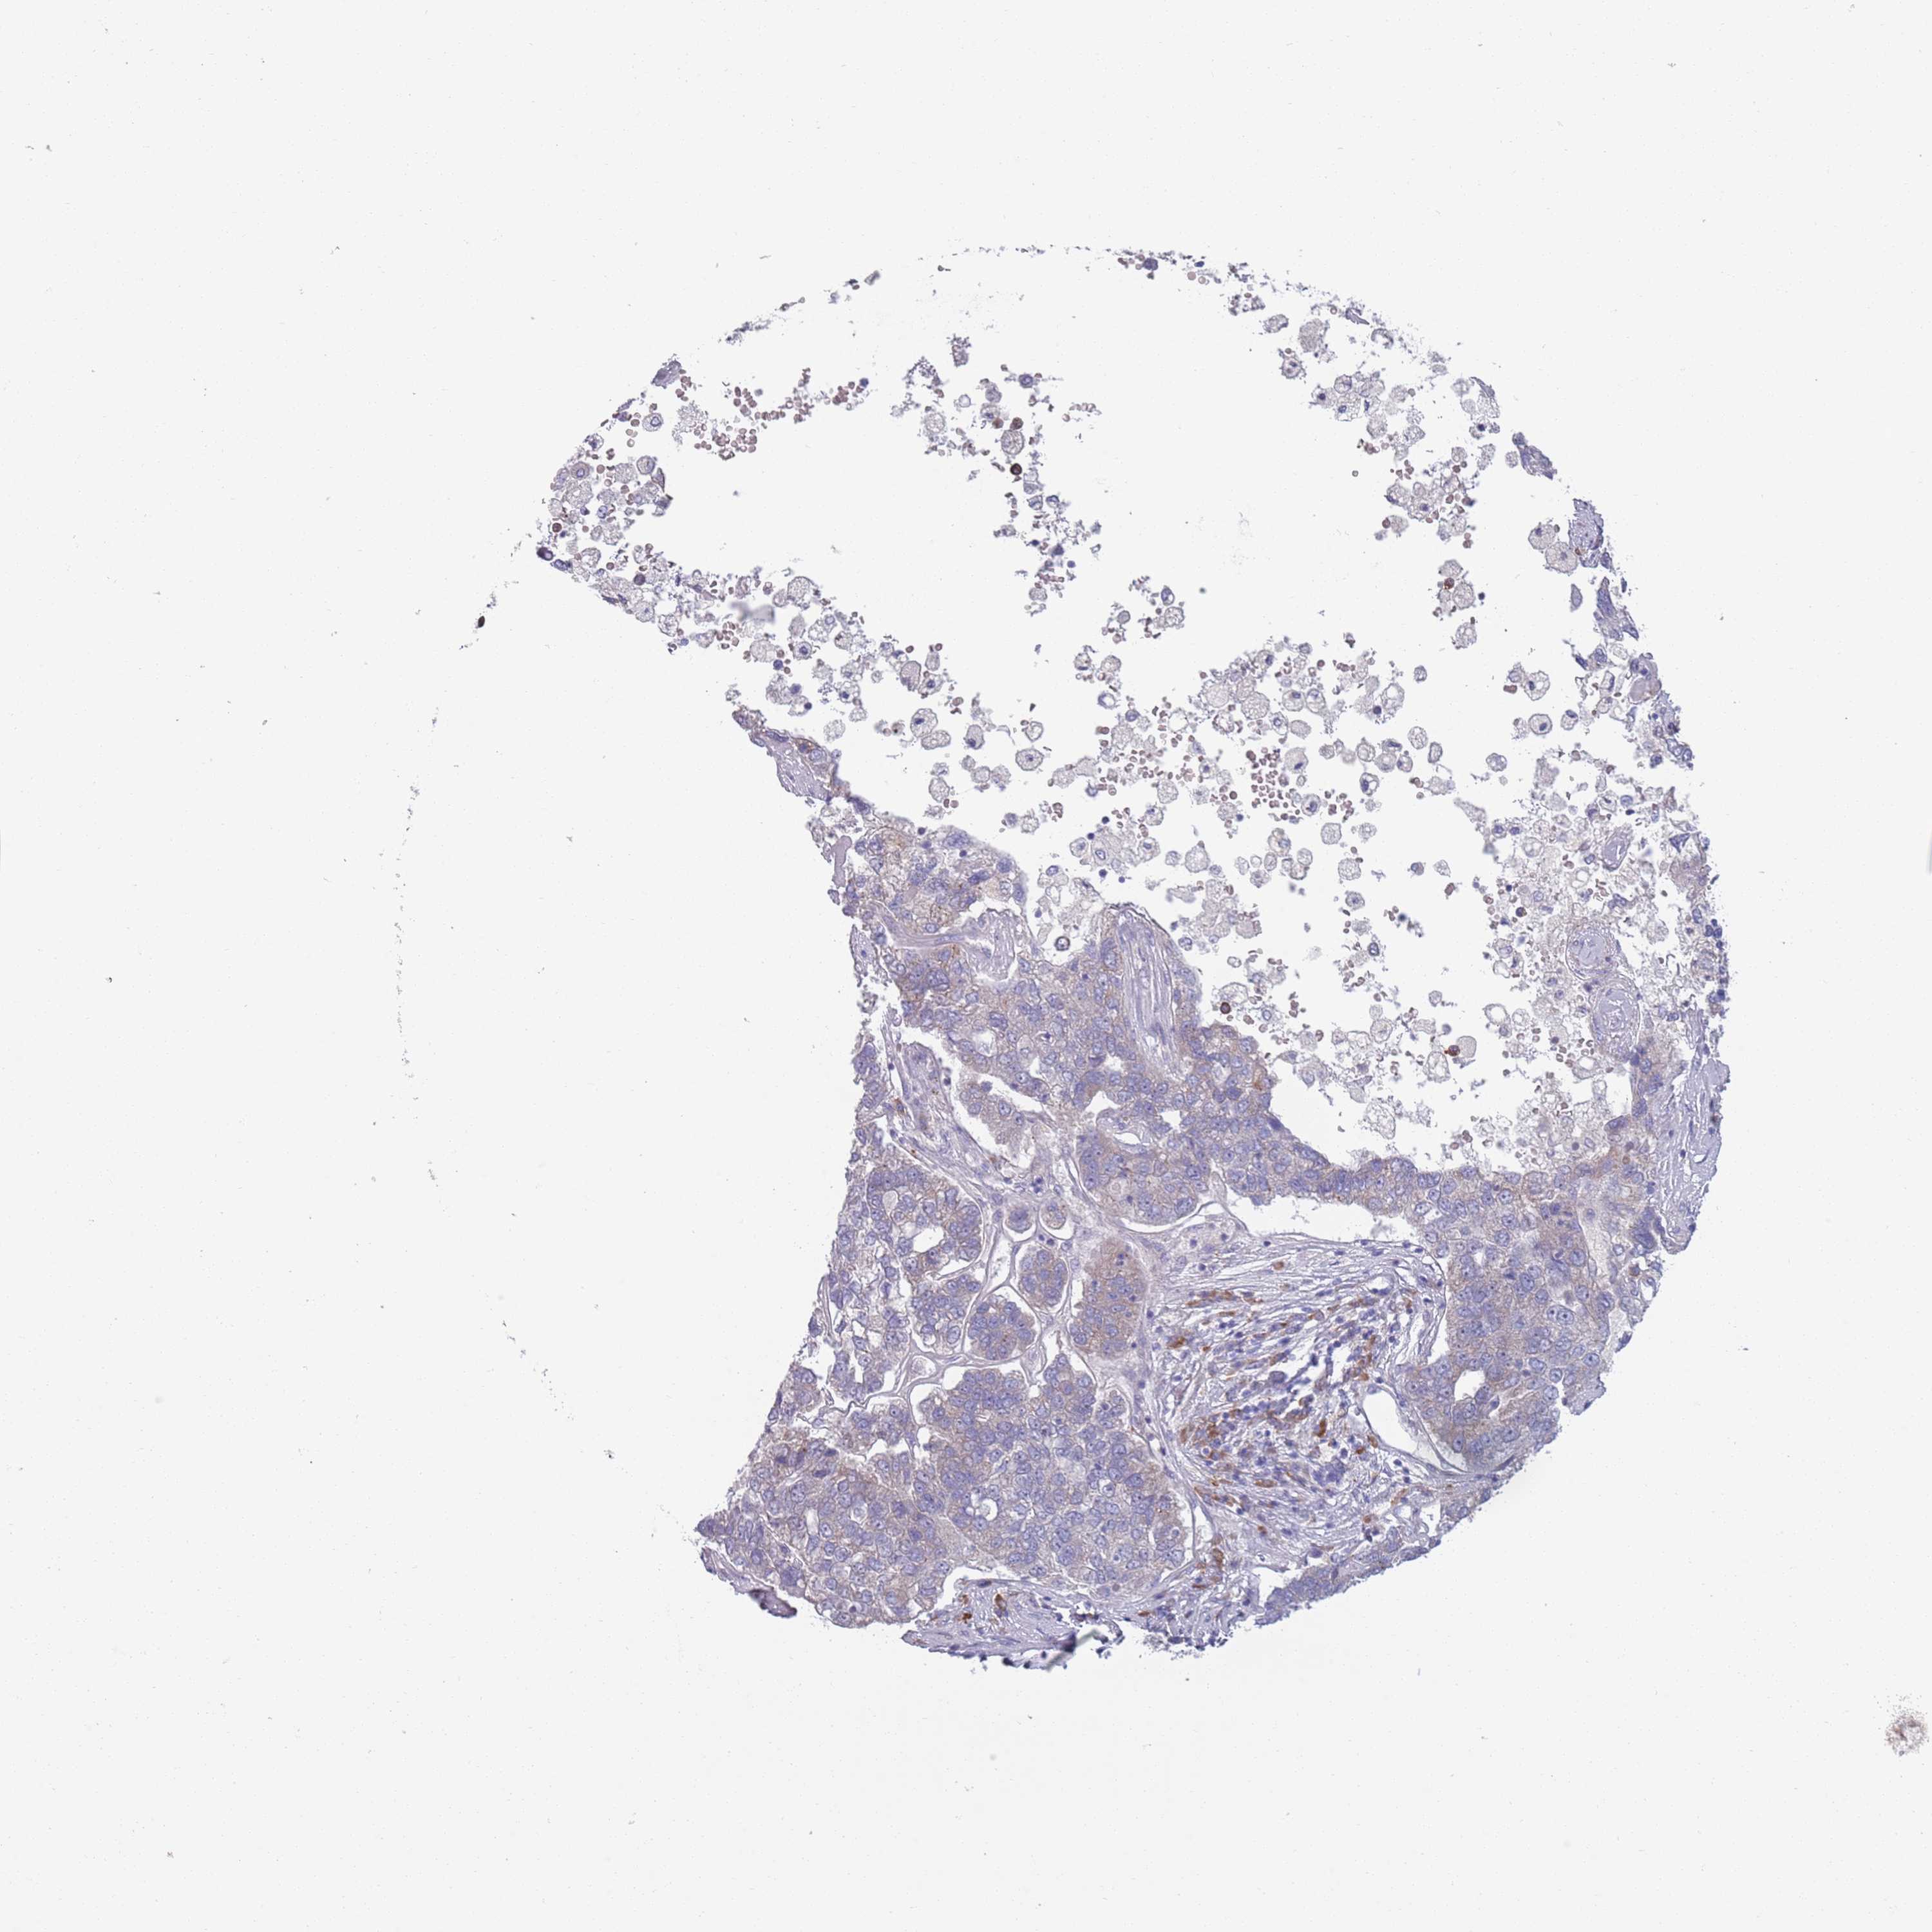

PANCREATIC CANCER - Protein expressioni

A mouse-over function shows sample information and annotation data. Click on an image to view it in a full screen mode. Samples can be filtered based on level of antibody staining by selecting one or several of the following categories: high, medium, low and not detected. The assay and annotation is described here.

Note that samples used for immunohistochemistry by the Human Protein Atlas do not correspond to samples in the TCGA dataset.

Antibody stainingi

Antibody staining in the annotated cell types in the current human tissue is reported as not detected, low, medium, or high, based on conventional immunohistochemistry profiling in selected tissues. This score is based on the combination of the staining intensity and fraction of stained cells.

Each image is clickable and will lead to virtual microscopy that enables deeper exploration of all samples and also displays staining intensity scores, fraction scores and subcellular localization as well as patient and tissue information for each sample.

Antibody HPA048884

Staining

High

Medium

Low

Not detected

Intensity

Strong

Moderate

Weak

Negative

Quantity

>75%

75%-25%

<25%

None

Location

Nuclear

Cytoplasmic/membranous

Cytoplasmic/membranous,nuclear

Adenocarcinoma, NOS